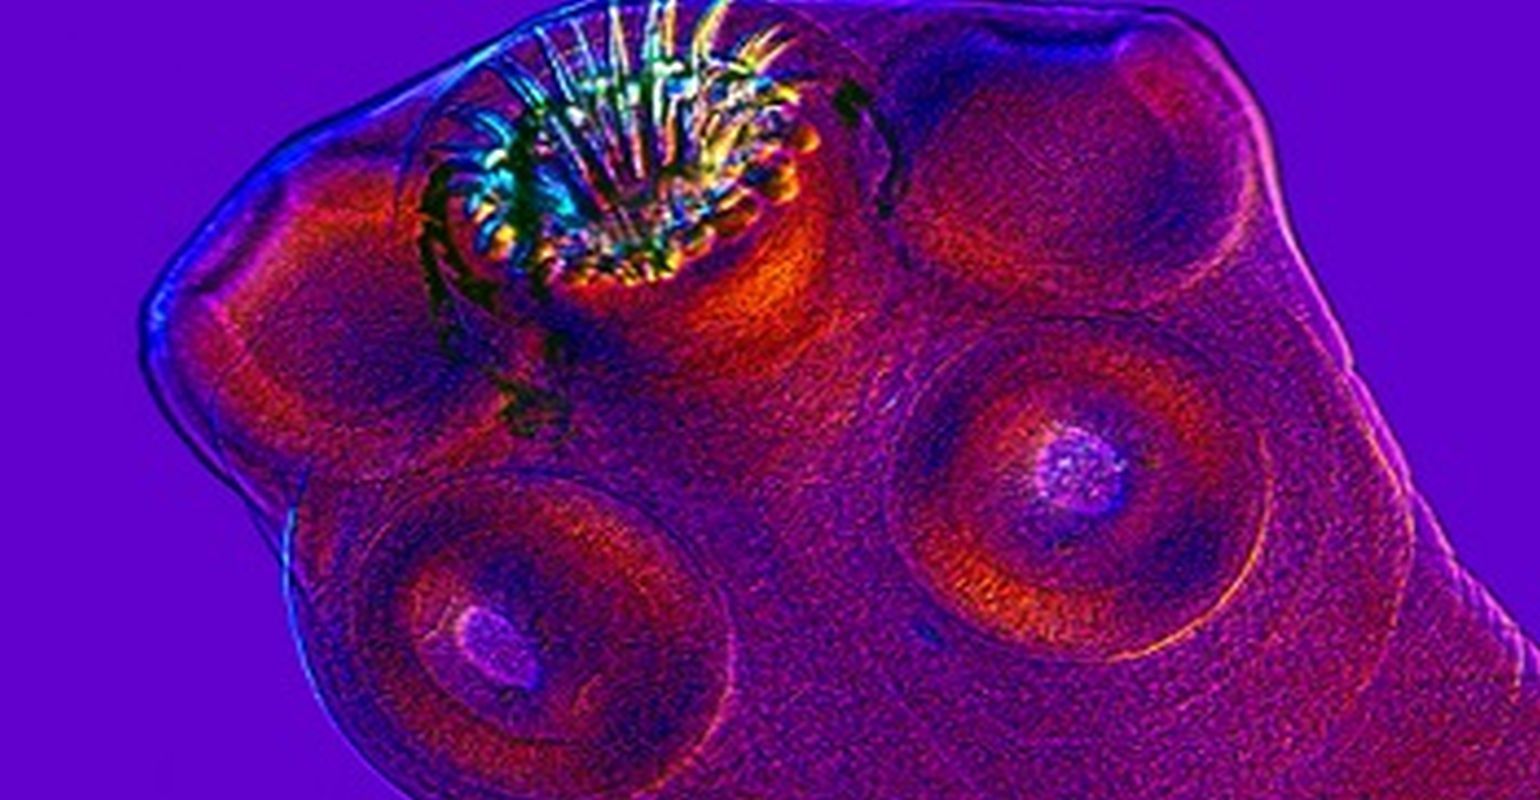

Neurocysticercosis most often spreads from person to person. The tapeworm eggs hatch in the intestine and spread throughout the body, including the brain, where they cause the most problems. When they reach the brain, they form cysts, leading to neurocysticercosis.

The imaging tests help determine the form of neurocysticercosis and therefore, treatment. Those who experience epileptic seizures (which can occur in anyone with neurocysticercosis) benefit from AEDs. Steroid and anti-parasitic medications may help speed up healing in people with a single live brain cyst. Those with multiple viable cysts should be treated with a combination of anti-parasitics. In other cases, the cyst can block a ventricle, which can be fatal and needs to be removed surgically using a minimally invasive procedure called neuroendoscopy. Some patients develop hydrocephalus (a buildup of cerebrospinal fluid in the brain) and may require a shunt to drain the fluid.